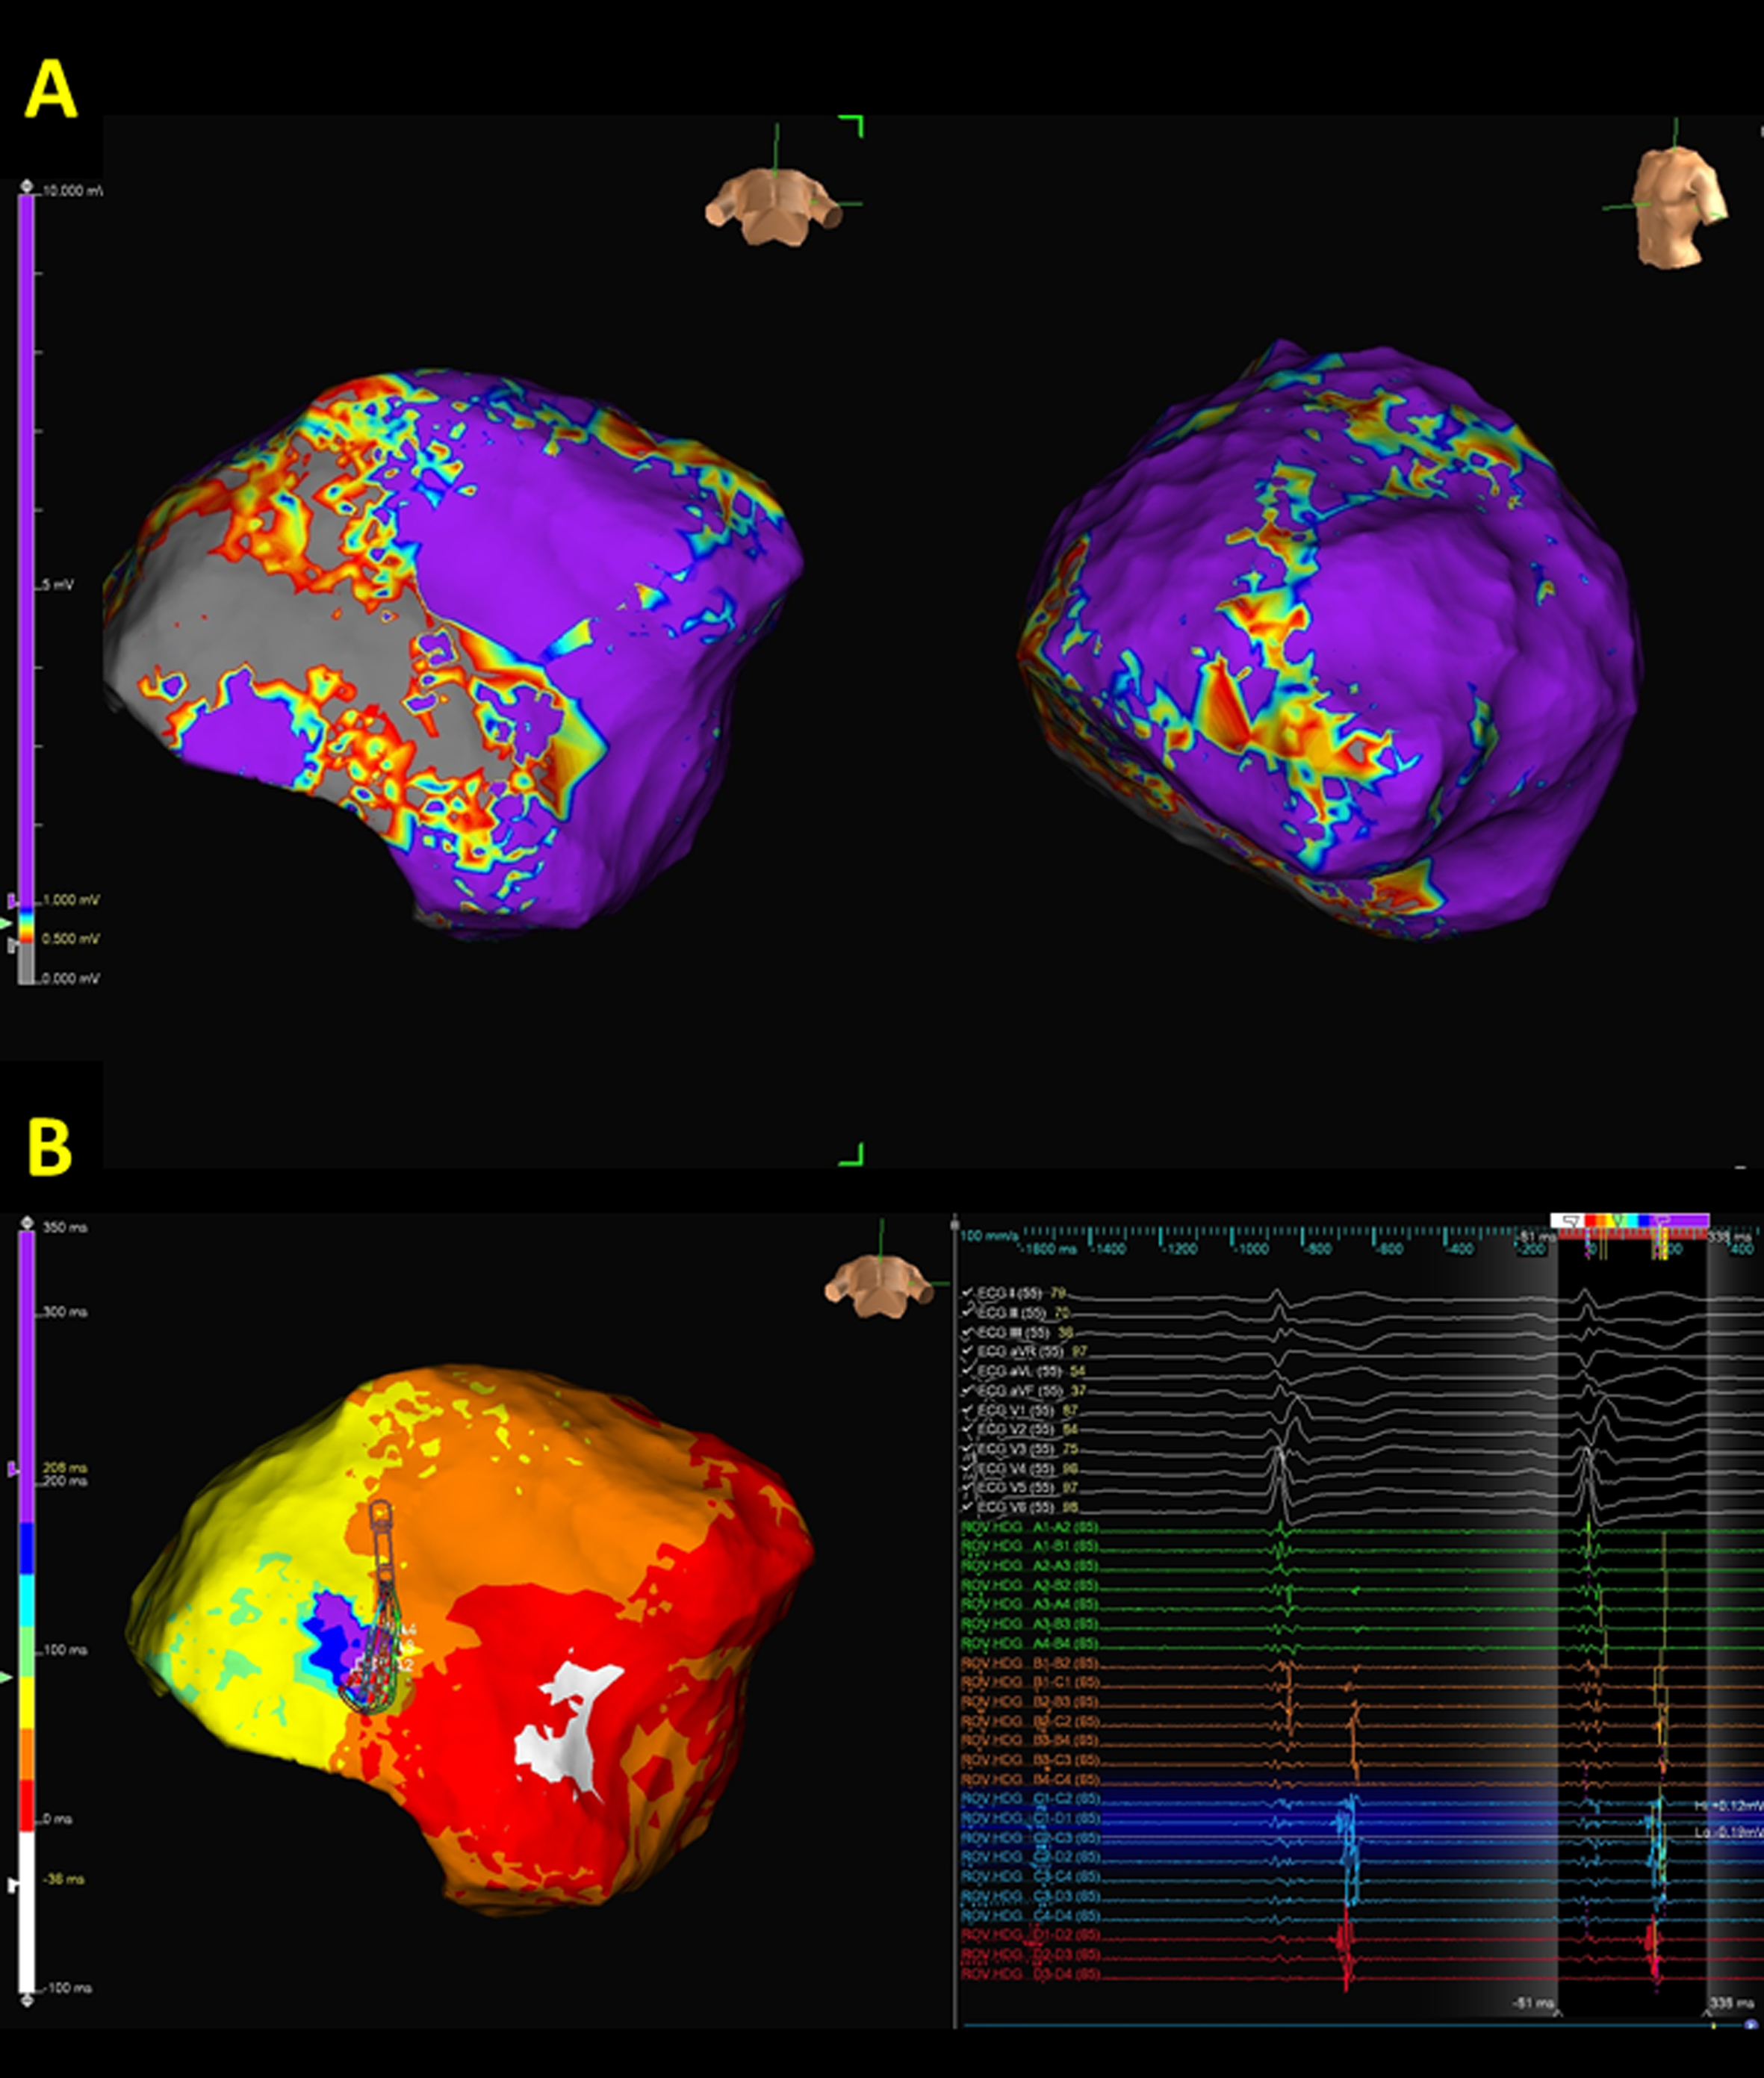

Since substrate mapping focused on bipolar voltage, electrogram duration, and fractionated or isolated late potentials, our group proposed a novel Simultaneous Amplitude Frequency Electrogram Transformation (SAFE-T) to recognize critical substrates correlated to the VT isthmus, and ablation targeting these abnormal substrates could yield better outcomes [25, 41, 42, 43]. Recently, functional substrate mapping has been proposed by annotating the offset of the local bipolar electrogram deflection to create isochronal late activation mapping (ILAM). The isochronal crowding regions, i.e., the deceleration zone identified by ILAM, are frequently correlated with the critical zone of VT circuits. Substrate modification based on the ILAM approach has been reported to be an effective and promising strategy to achieve noninducibility of VT [44, 45]. A representative case using ILAM to localize the critical zone of VT circuits is illustrated in Fig. 2.

Fig. 2.

Fig. 2.A representative case demonstrates the correlation between

epicardial substrate and isochronal late activation map (ILAM) in arrhythmogenic

right ventricular cardiomyopathy (ARVC). (A) An extensive scar is observed

within the inferior wall of the basal to middle right ventricle (RV). However, no

remarkable channels could be identified. (B) The creation of an ILAM demonstrated

the functional property of abnormal substrates during sinus rhythm. The latest

deflection of the bipolar electrograms was annotated. The activation sequence

initiated from white, red, orange, yellow, green, blue, indigo, to violet region

and the propagation wavefront slowed down in the isochronal crowding area during

sinus rhythm (Supplementary Movie 1). The isochronal crowding region

(deceleration zone) identified within the scar was defined by regions with

isochronal crowding with